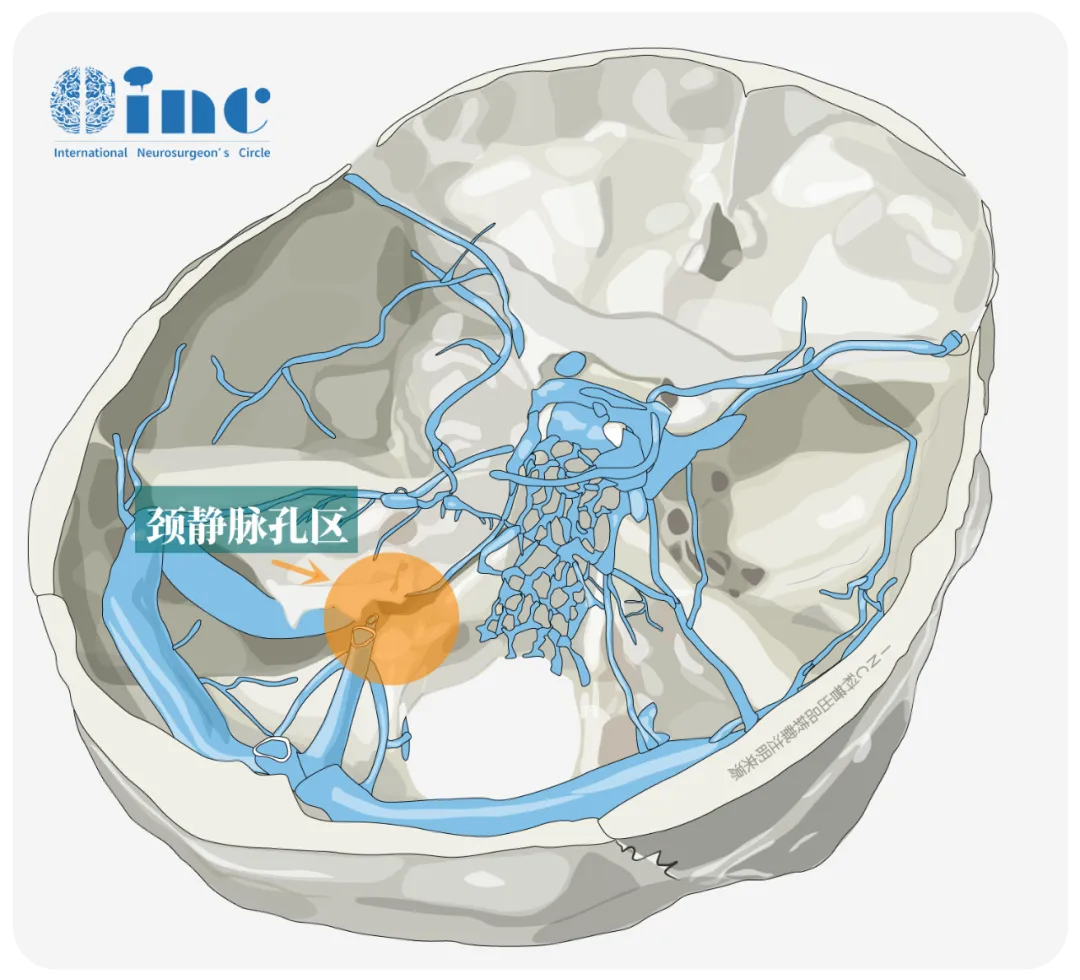

“工欲善其事,必先利其器”,神经解剖是神经外科医生手术的基础。现在的我们早已熟知我们的大脑究竟有哪些构成。而今天我们的话题将讨论,“”,颈静脉孔区——沟通颅内外的重要且复杂的神经血管孔道。

颈静脉孔区为何如此复杂?

颈静脉孔由前外侧的颞骨岩部和后内侧的枕骨围成,分为较大的居后外侧的静脉部和较小的居前内侧的神经部,两部中间有纤维桥或骨桥分开。内覆各类神经血管穿行,包括颈内静脉、岩下窦、枕动脉脑摸支、咽升动脉脑膜支、舌咽神经、迷走神经、副神经等毗邻。少数(6%~25%)舌咽神经经神经部之前独自的骨管出颅。

覆盖颈静脉孔的硬脑膜有2个特征性的穿孔,分别形成漏斗状的舌咽神经道和筛网状的迷走神经道,前者有舌咽神经穿过,后者有迷走神经和副神经穿过,两道间通常有宽约0.5~4.9mm的硬膜隔。由于舌咽、迷走神经起点邻近,且常有蛛网膜粘连,因而在脑干附近或蛛网膜下腔很难将二者确切分开,唯有在舌咽神经道与迷走神经道间的硬膜隔处方可分辨。

颈静脉孔大概可分为三个部分:乙状窦部分、岩下窦部分、颅神经部分(舌咽神经、迷走神经、副神经)。